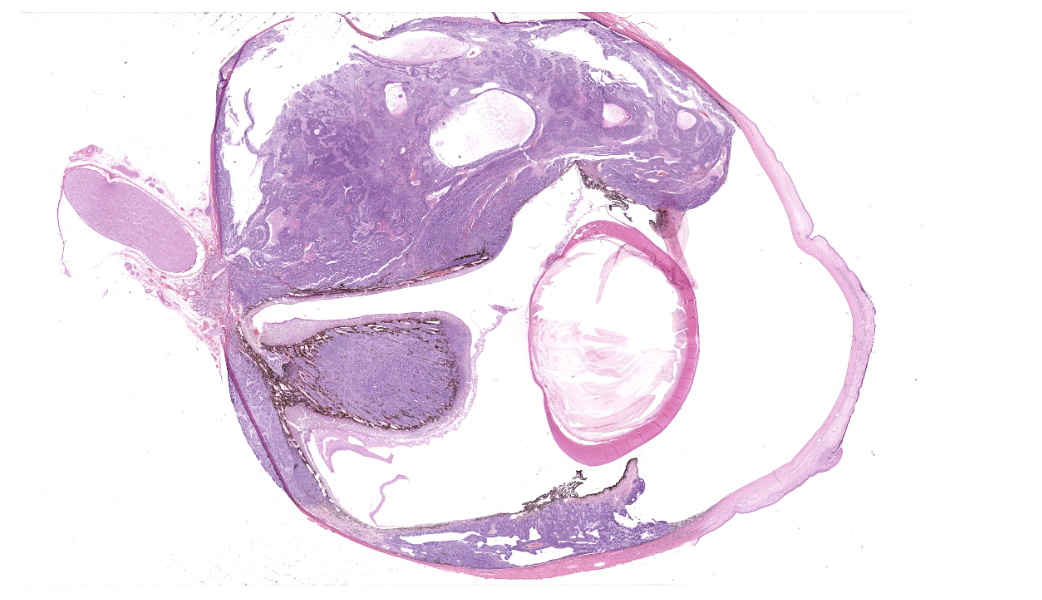

Gross Pathology: On external examination, the eye is notably buphthalmic. The cornea is centrally ulcerated and opaque. On cut surface, a tan, soft mass with multifocal cystic spaces extends from the ventral choroid, protrudes into the anterior and posterior chambers, and abuts and minimally displaces the lens dorsally. The ventral iris is not observed.Laboratory Results:

Expanding the anterior uvea, effacing the iris, and markedly expanding the suprachoroidal space is a densely cellular, unencapsulated neoplasm of neuroepithelial cells. Neoplastic cells are arranged in variably dense sheets and as palisading columnar cells surrounding a central lumen (Flexner-Wintersteiner rosettes) or surrounding eosinophilic fibrillar material (Homer-Wright rosettes) surrounded by collagenous and occasionally myxomatous stroma. Neoplastic cells are polygonal to fusiform, have a high nuclear to cytoplasmic ratio, and have distinct cell borders. The nuclei are round to ovoid, finely stippled, and have indistinct nucleoli. There are 16 mitoses in 10 high power fields and anisokaryosis is mild. The neoplastic cells are impinging upon the optic nerve, which has multifocal axonal degeneration and is infiltrated by a population of histiocytes, lymphocytes, and plasma cells, as well as scattered foci of hemorrhage. The retina has multifocal, disorderly components of viable photoreceptor and retinal ganglion cells, dense necrosis, glial scarring, and presumed Mueller cells. The retina is diffusely detached and lacks apparent retinal vessels. The retinal pigment epithelial cells have multifocally migrated through to the inner layers of the retina. The cortical lens fibers are moderately liquefied and homogenous and there is posterior migration of the lens epithelium, consistent with cataractous change. The corneal epithelium has marked, segmental ulceration and the outer corneal stroma in this area is mineralized with occasional breaks and is densely compact with fibrosis. Multifocally throughout the corneal stroma are areas of fibrosis, vascularization, and scattered neutrophils.Contributor's Morphologic Diagnoses:

Eye: Medulloepithelioma, Cataractous change, Ulcerative and neutrophilic keratitis, Stromal fibrosis and mineralization, Diffuse, severe retinal atrophy, Suspect avascular retina, Moderate optic nerve degeneration and necrosis.Contributor's Comment:

Globe, choroid, ciliary body, and iris: Medulloepithelioma.JPC Comment: